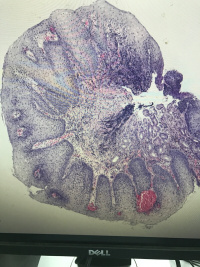

食道粘膜

腹痛,距门齿33cm处食管壁见0.4✖️0.5cm隆起

灰白组织一粒,直径0.1

鳞状上皮乳头状瘤性息肉,局部鳞状上皮轻度异型增生。

鳞状上皮下是幽门腺,胃粘膜异位

鳞上皮乳头上移,副基底层增生